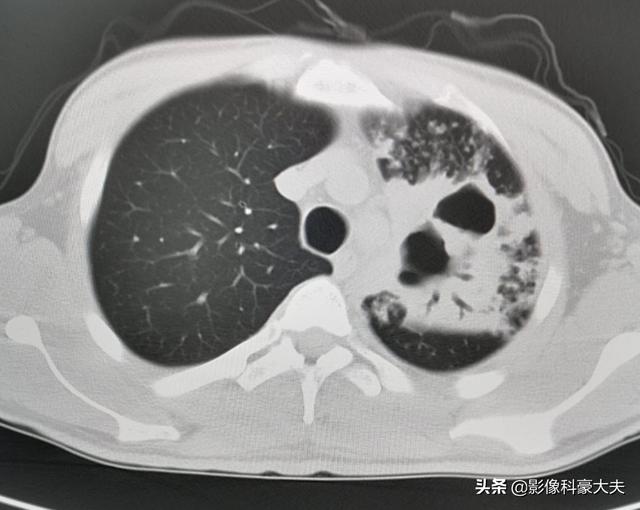

この患者は30歳を過ぎたばかりで、血糖値は20を超えていた。結核の二次感染で、左側の肺組織が大規模に破壊され、大きな空洞が多数形成され、血を吐いていた。

免疫機能が低下した糖尿病患者は、黄色ブドウ球菌、アスペルギルス、結核菌、肺炎桿菌などの感染症にかかりやすい。

このチャップはOKで、1年間計画的に治療した結果、病巣はかなり吸収された。